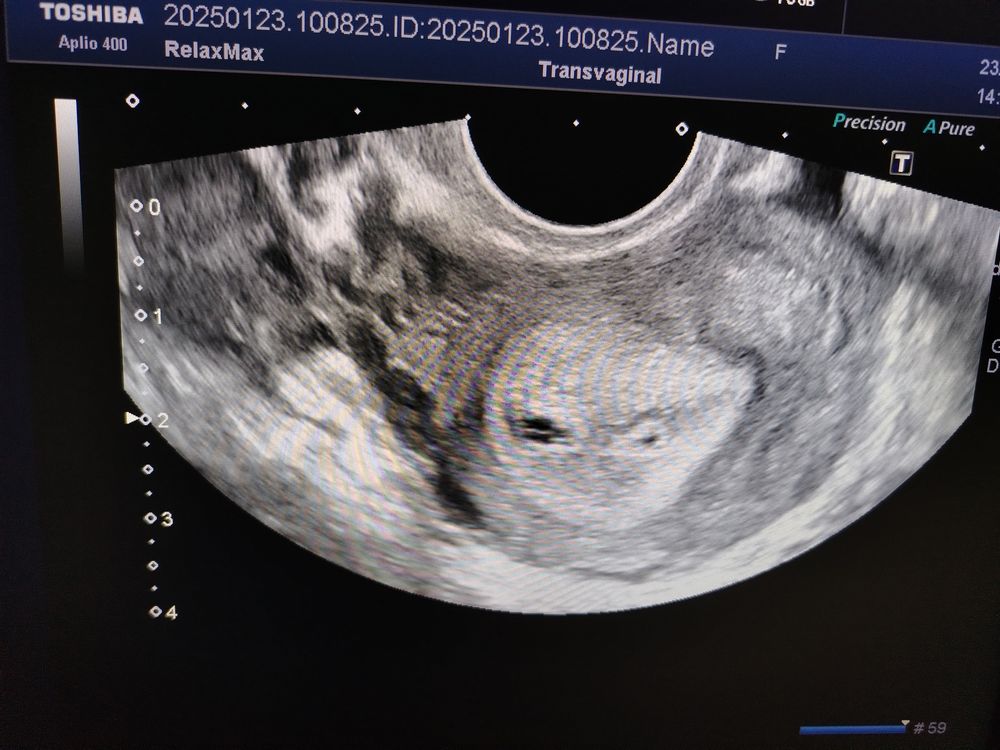

Одно или два плодных яйца?

УЗИ, КТГ, доплер

Подскажите кто сталкивался

Сердцебиение или ЗБ ПЯ не опустилось в матку со слов гинеколога